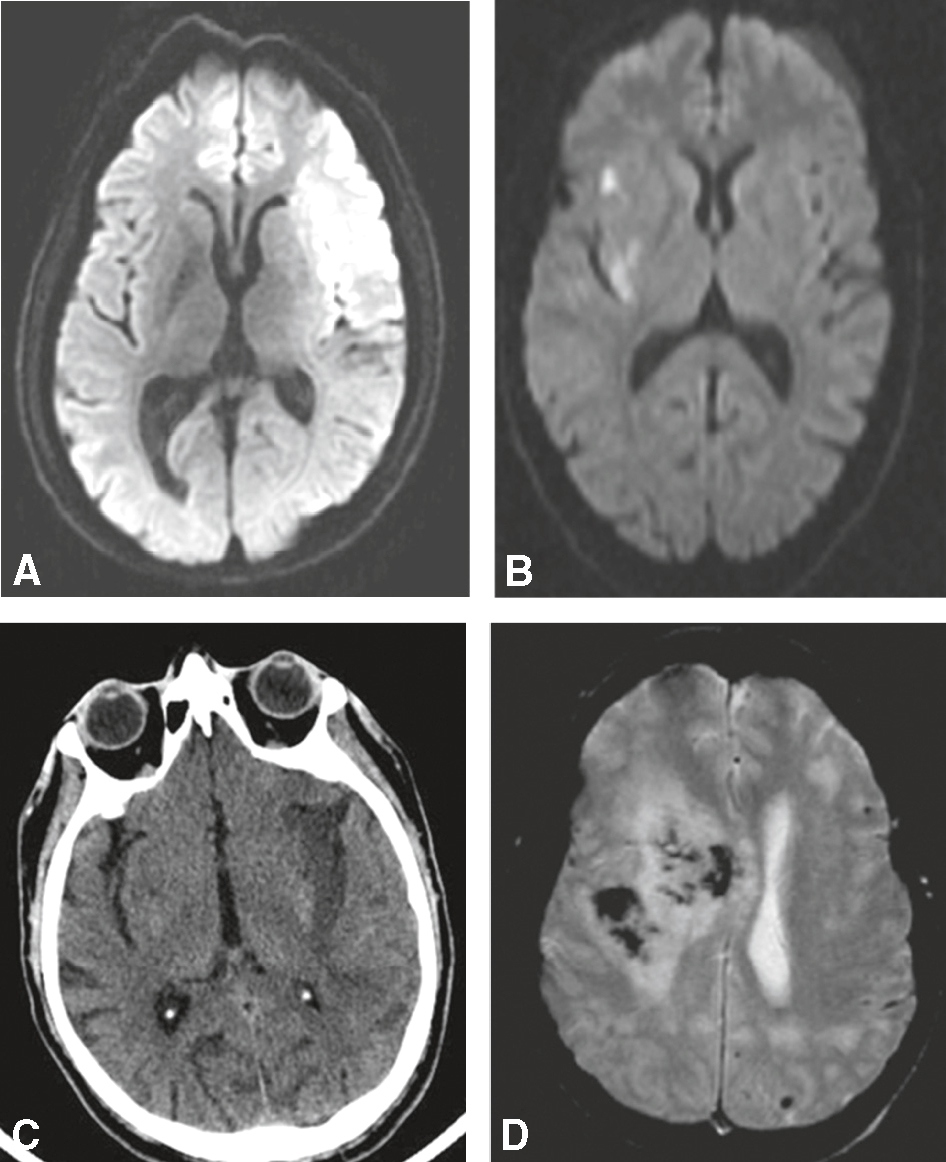

• tout déficit neurologique brutal ou aigu doit faire suspecter un AVC et nécessite une imagerie cérébrale en urgence (fig. 5.1);

Fig. 5.1

Déficit récent par accident vasculaire cérébral : imagerie cérébrale.

A. IRM cérébrale (diffusion). Infarctus sylvien gauche (hypersignal). B. IRM cérébrale (diffusion). Infarctus sylvien droit (hypersignal). C. Scanner cérébral sans injection. Infarctus sylvien gauche (hypodensité). D. IRM cérébrale (T2*, ou écho de gradient). Hémorragie cérébrale frontale droite (hyposignal).L'image montre quatre scans cérébraux, étiquetés de A à D, utilisés pour diagnostiquer et évaluer les accidents vasculaires cérébraux (AVC). Image A : Une IRM en diffusion montrant une zone hyperintense dans l'hémisphère droit, indiquant une restriction de diffusion typique d'un AVC ischémique aigu. Image B : Une autre IRM en diffusion avec une zone hyperintense plus petite, suggérant un AVC ischémique plus récent ou moins étendu. Image C : Une tomodensitométrie (CT scan) montrant une hypodensité dans l'hémisphère gauche, typique d'un AVC ischémique chronique. Image D : Une IRM en séquence T2* montrant une hémorragie intracérébrale avec une zone hypointense due à la désoxyhémoglobine, indiquant un AVC hémorragique. Ces images illustrent différentes présentations d'AVC, permettant aux professionnels de la santé de déterminer le type d'AVC et de planifier le traitement approprié. L'IRM en diffusion est particulièrement utile pour détecter les AVC ischémiques aigus en raison de sa sensibilité à la restriction de diffusion. En résumé, l'image montre des exemples d'AVC ischémique aigu, d'AVC ischémique récent, d'AVC ischémique chronique, et d'AVC hémorragique, offrant un aperçu complet des types d'AVC et de leurs caractéristiques distinctives sur les scans cérébraux.